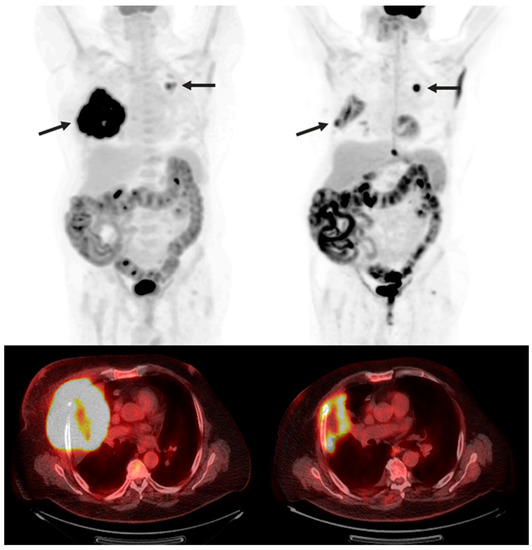

The subtypes have several differences that influence their management. CM metastasizes via the lymph system, most commonly to the lungs, liver, and brain. UM spreads via the circulatory system, owing to the extensive vasculature of the eye, most commonly to the liver [36] (Figure 2). Unlike CM, which is commonly detected via dermatological exam, primary UM sometimes presents with ocular symptoms when it invades the eye tissues, including blurred vision and seeing shadows [36].

Figure 2.

A 69-year-old woman with uveal melanoma metastatic to the liver post-treatment with tebentafusp, a bispecific antibody (BsAb), who developed cytokine release syndrome without radiologic imaging manifestations. Her large-burden liver disease was largely stable over the course of almost 3 years.